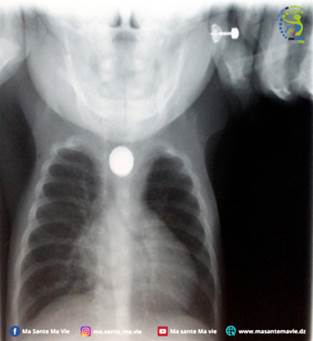

وأظهرت صورة الأشعة وجود جسم معدني دائري في المريء مؤكدة وجود البطارية. أين تم نقل الطفل فوراً إلى قسم جراحة الأطفال وكشف التصوير المقطعي عن نخر في جدار المريء مع وجود ثقب، وهو من المضاعفات الخطيرة.